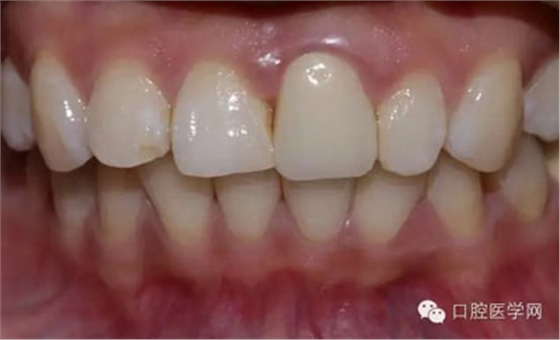

術(shù)前照

檢查:21金屬烤瓷冠修復(fù),顏色及形態(tài)與鄰牙不協(xié)調(diào),牙齦有輕微發(fā)黑,扣痛(-)、松動(dòng)度(-);11近中鄰面齲壞